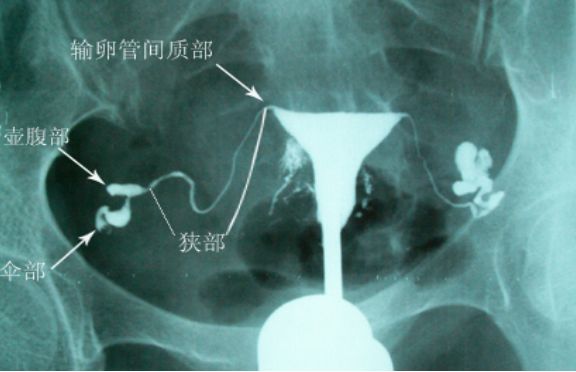

经X线的输卵管介入复通术是在数字X光机下医生通过电视屏直视下采用同轴导管系统,经阴道、宫颈、子宫、子宫角向输卵管插入输卵管导管,进行输卵管选择性造影,再依据输卵管的具体堵塞部位和具体情况经输卵管导管向输卵管插入输卵管导丝,通过导管丝对于堵塞的输卵管进行复通分离的治疗过程。

主要用于输卵管不通,特别是输卵管间质部及峡部粘连阻塞等。

造影视:双侧输卵管近段狭窄,右侧伞端通而不畅,左侧输卵管管壁不规则,通而不畅。

依次开通右侧输卵管+灌注药物,左侧输卵管+灌注药物,造影,显示左侧输卵管完全通畅。